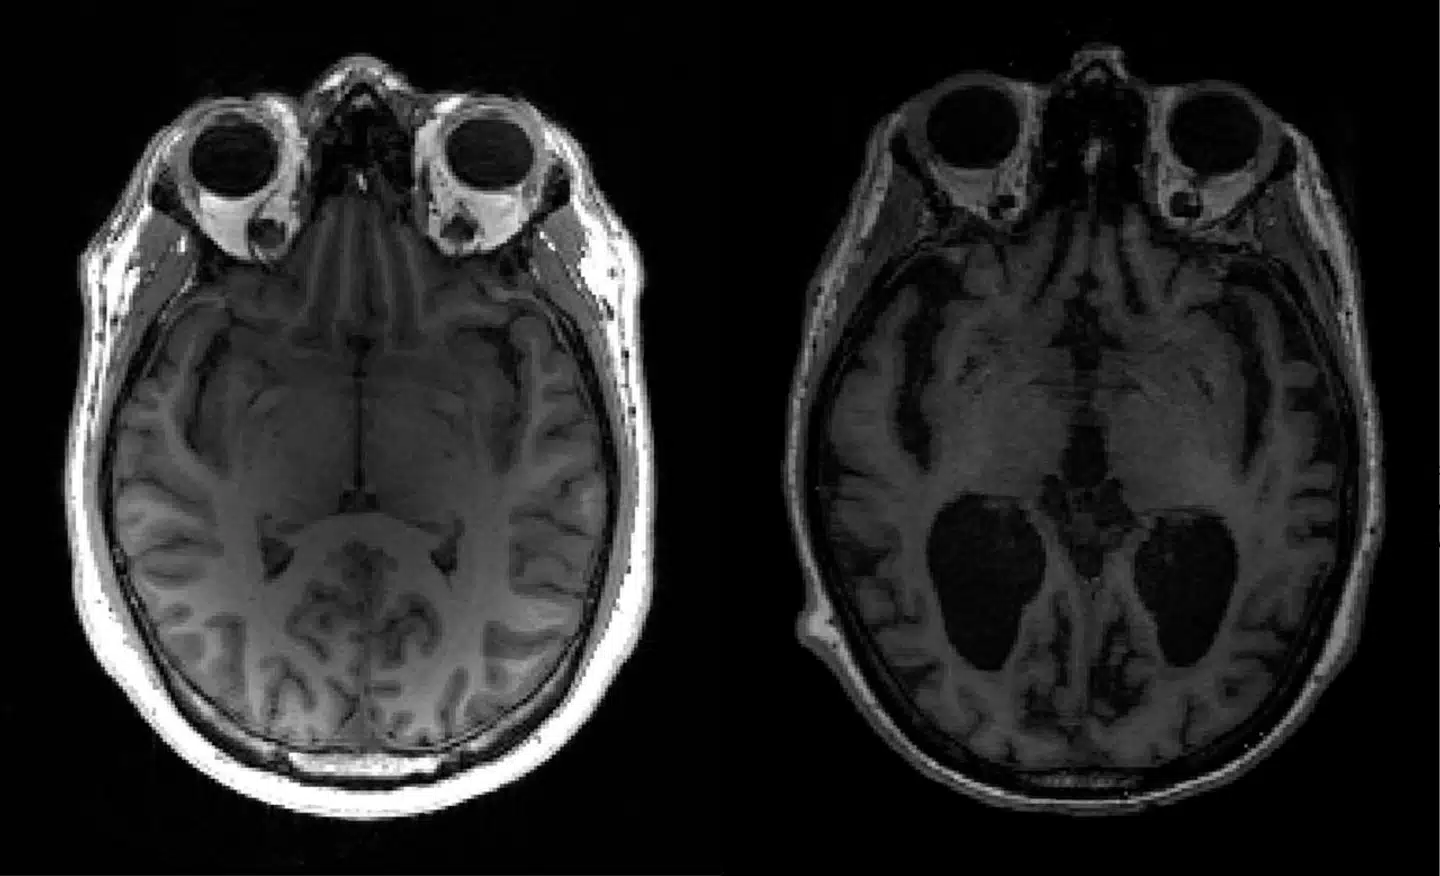

Selvom Madeleine Paldo er 100 år, er hendes hjerne langt friskere end det.

Den passer til en krop, der var tre årtier yngre, vurderer eksperter.

100-årige Madeline Paldo og 85-årige Carol Siegler har langt bedre hjerner end de fleste på deres alder. De er en del af en helt særlig gruppe kaldet »superseniorer«. Forskere har i et årti forsøgt at gennemskue, hvad der er så specielt ved disse ældre – særligt én ting går igen, lyder det fra forskerne.